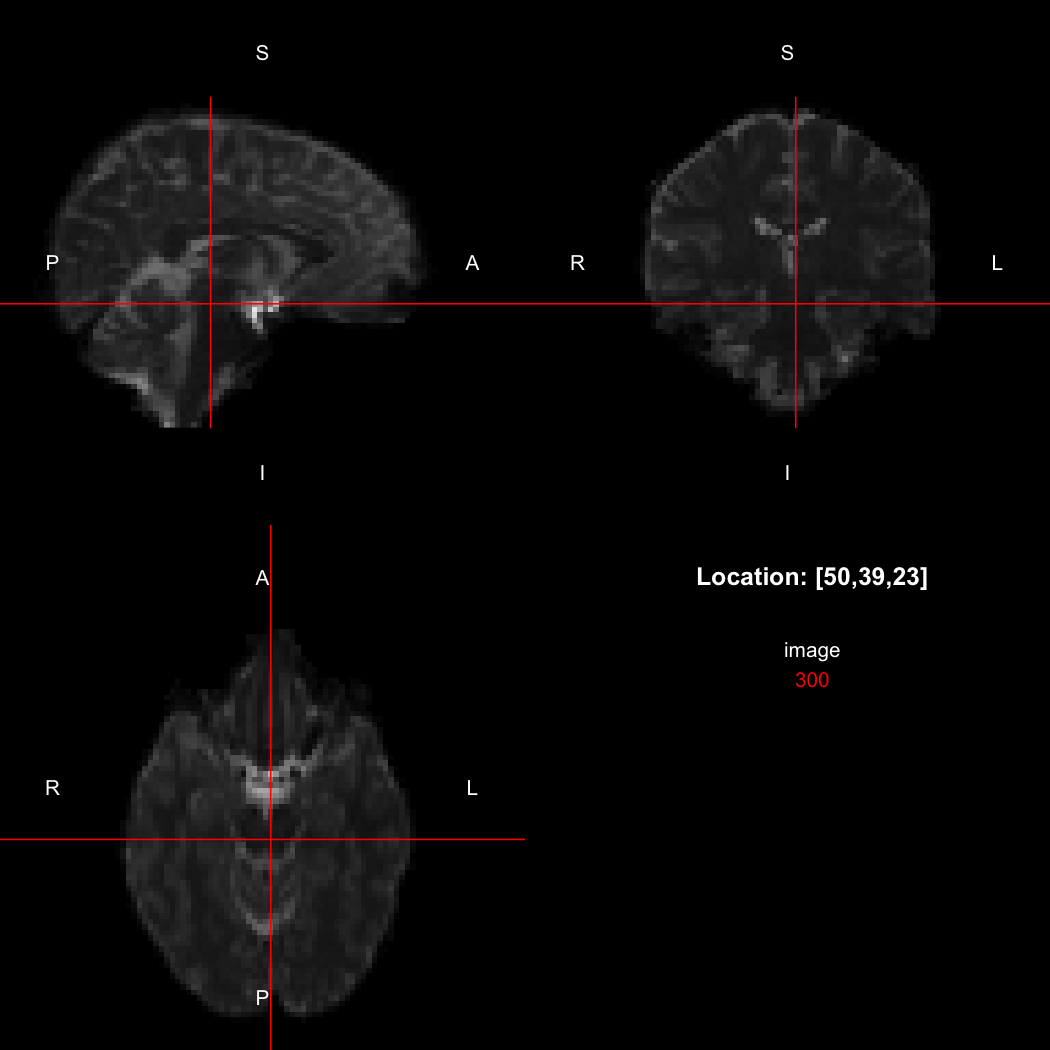

## [1] "LAS"So, here, “LAS” means that the positive x-axis points left, the positive y-axis anterior and the positive z-axis superior. This is the so-called “radiological” orientation convention, and can be requested when viewing images for those who are used to it:

view(image, radiological=TRUE)

Notice the left (L) and right (R) labels, relative to the view shown

above. Setting the radiologicalView option to

TRUE will make this the default for all future views.